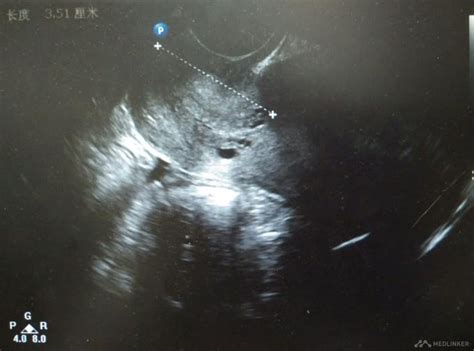

子宫体积增大

做黑白B超 显示子宫大于正常

月经前子宫内膜是最厚的,子宫内膜大于1.2以上就该来月经了,如果来月经了问题也不会很大,如果不是月经前,跟你周期不符合,那子宫内膜是太厚了,得检查子宫内膜过厚的原因,正常子宫内膜在8-10MM才合适正常怀孕的;而且还有一个原因,有停经没有,早孕也会出现子宫增大和子宫内膜增厚的,而在孕30天前B超是看不到妊娠迹象的;